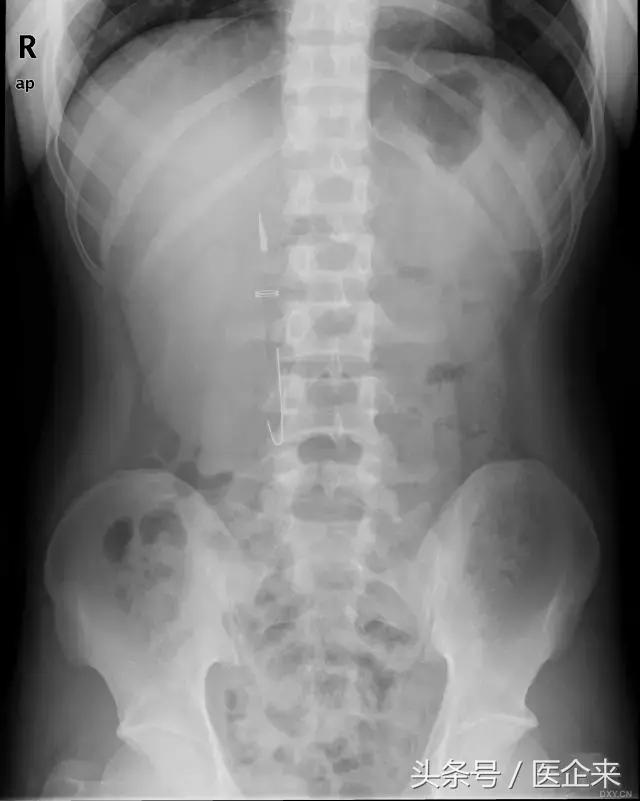

1. 一支圆珠笔从肛门进入(对不起,小编又污了...)

2. 一支钢笔经口进入(看来他/她真的很想做文化银啊~)

3.磁性手镯经口进入(心疼这个2岁的小宝宝,做手术要遭多大罪啊!)

5. 一根长长的毛线针,从肛门进入(想想就觉得菊部疼痛...)